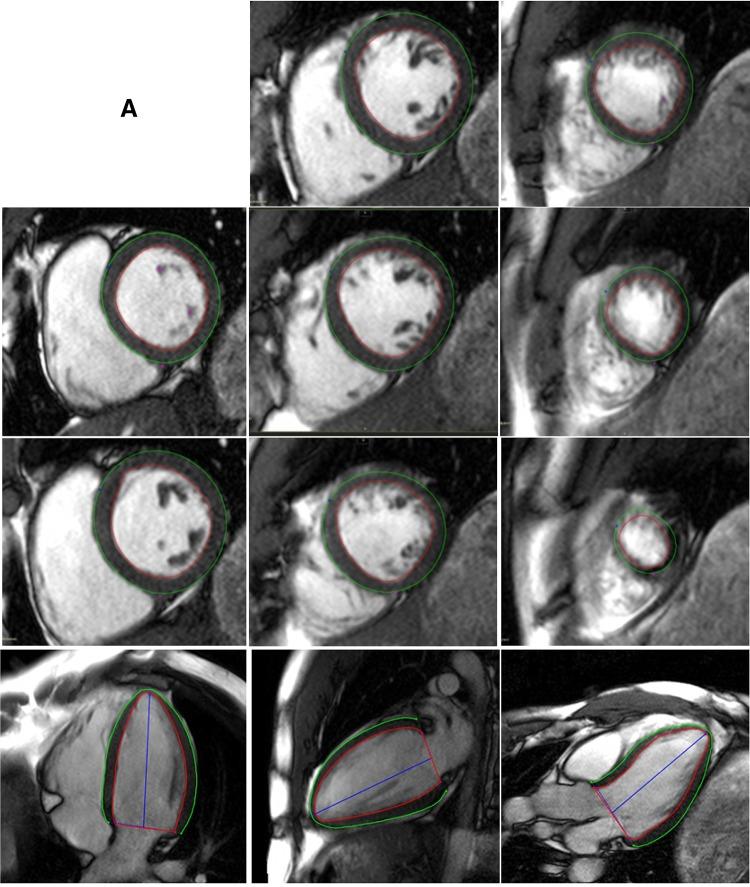

Myocardial deformation is a sensitive marker of sub-clinical myocardial dysfunction that carries independent prognostic significance across a broad range of cardiovascular diseases. It is now possible to perform 3D feature tracking of SSFP cines on cardiac magnetic resonance imaging (FT-CMR). This study provides reference ranges for 3D FT-CMR and assesses its reproducibility compared to 2D FT-CMR. One hundred healthy individuals with 10 men and women in each of 5 age deciles from 20 to 70 years, underwent 2D and 3D FT-CMR of left ventricular myocardial strain and strain rate using SSFP cines. Good health was defined by the absence of hypertension, diabetes, obesity, dyslipidaemia, or any cardiovascular, renal, hepatic, haematological and systemic inflammatory disease. Normal values for myocardial strain assessed by 3D FT-CMR were consistently lower compared with 2D FT-CMR measures [global circumferential strain (GCS) 3D - 17.6 ± 2.6% vs. 2D - 20.9 ± 3.7%, P < 0.005]. Validity of 3D FT-CMR was confirmed against other markers of systolic function. The 3D algorithm improved reproducibility compared to 2D, with GCS having the best inter-observer agreement [intra-class correlation (ICC) 0.88], followed by global radial strain (GRS; ICC 0.79) and global longitudinal strain (GLS, ICC 0.74). On linear regression analyses, increasing age was weakly associated with increased GCS (R = 0.15, R = 0.38), peak systolic strain rate, peak late diastolic strain rate, and lower peak early systolic strain rate. 3D FT-CMR offers superior reproducibility compared to 2D FT-CMR, with circumferential strain and strain rates offering excellent intra- and inter-observer variability. Normal range values for myocardial strain measurements using 3D FT-CMR are provided.

心肌形变是亚临床心肌功能障碍的敏感标志物,在广泛的心血管疾病中具有独立的预后意义。现在可以在心脏磁共振成像(FT-CMR)上对稳态自由感应衰减(SSFP)电影进行三维特征跟踪。本研究提供了三维FT-CMR的参考范围,并评估了其与二维FT-CMR相比的可重复性。100名健康个体,年龄在20至70岁之间,分为5个年龄组,每组10名男性和10名女性,使用SSFP电影进行左心室心肌应变和应变率的二维和三维FT-CMR检查。健康状况良好的定义为无高血压、糖尿病、肥胖、血脂异常或任何心血管、肾脏、肝脏、血液和全身性炎症性疾病。与二维FT-CMR测量相比,三维FT-CMR评估的心肌应变正常值始终较低[整体圆周应变(GCS)三维-17.6±2.6%,二维-20.9±3.7%,P<0.005]。三维FT-CMR的有效性通过与其他收缩功能标志物对比得到证实。与二维算法相比,三维算法提高了可重复性,其中GCS的观察者间一致性最佳[组内相关系数(ICC)为0.88],其次是整体径向应变(GRS;ICC为0.79)和整体纵向应变(GLS,ICC为0.74)。在线性回归分析中,年龄增长与GCS升高(R=0.15,R=0.38)、收缩期峰值应变率、舒张期末期峰值应变率升高以及收缩期早期峰值应变率降低呈弱相关。与二维FT-CMR相比,三维FT-CMR具有更高的可重复性,圆周应变和应变率在观察者内和观察者间的变异性都很小。本文提供了使用三维FT-CMR测量心肌应变的正常范围值。